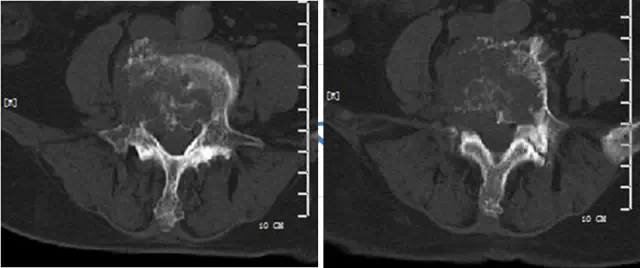

影像学所见:

腰椎:L4椎体及右侧椎弓根骨质破坏。

我院专家组还介绍到,肺癌的转移途径有很多种,如:淋巴结转移、胸膜受侵和/转移、上腔静脉综合征、肾脏转移、消化道转移、骨转移、中枢神经系统症状、心脏受侵和转移、周围神经系统症状。